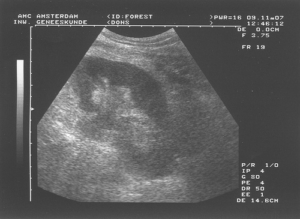

レントゲンやエコー検査などの画像診断も定期的に行った方がいいと思います。

頻度はその猫の症状によってなのですが、初回にはできれば実施したほうがいいと思います。